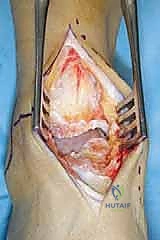

الخطوات الجراحية التفصيلية لزراعة مفصل HINTEGRA

تُجرى العملية عادة تحت التخدير النصفي أو العام، وتستغرق حوالي الساعتين إلى ثلاث ساعات. الدقة هنا تقاس بالمليمترات وأجزاء الدرجة الزاوية.

1. الشق الجراحي والوصول للمفصل

يقوم الجراح بإجراء شق أمامي طولي (Anterior Approach) في منتصف الكاحل. يتم إبعاد الأوتار والأوعية الدموية والأعصاب بعناية فائقة (هنا تتجلى أهمية مهارات الجراحة الدقيقة التي يمتلكها الدكتور هطيف) للوصول إلى محفظة المفصل.

2. إزالة الزوائد العظمية وتحرير المفصل

يتم إزالة النتوءات العظمية (Osteophytes) التي تسبب الألم وتحد من الحركة، وتحرير الأنسجة المتليفة لاستعادة المرونة الأولية للمفصل.